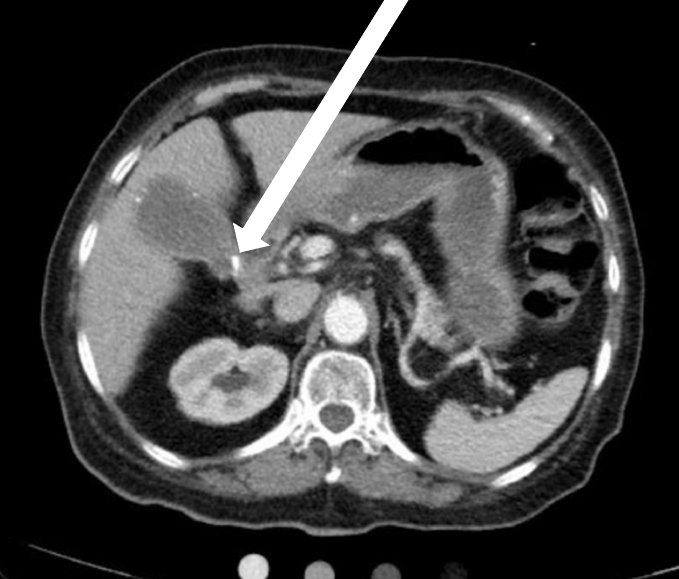

A 75-year-old female presented for evaluation of elevated liver function tests (LFTs). Upon arrival, she had no acute complaints with unremarkable vital signs, aside from elevated blood pressure of 155/79 mmHg. Review of LFTs demonstrated elevation of total bilirubin, aspartate aminotransferase (AST), alanine aminotransferase (ALT), and alkaline phosphatase (ALP). Physical examination and review of systems were unremarkable. POCUS revealed common bile duct dilatation with cholelithiasis and sludge. While these findings may be confused with a WES sign, POCUS also revealed a hyperechoic gallbladder wall (GBW) with shadowing and irregular clumps of echo. The hyperechoic GBW with irregular shadowing heightened the suspicion for PGB. Computed tomography scan confirmed the presence of PGB. The patient had a stent placed near the common hepatic duct stricture and was advised to return for cholecystectomy. She was readmitted three months later due to bacteremia, likely caused by gallbladder obstruction in the setting of gallbladder cancer.

Point of care ultrasound can be used to identify PGB. Because PGB has been associated with gallbladder carcinoma, prompt diagnosis is vital in early and aggressive treatment. In this case report, we demonstrate a reliable method in properly diagnosing PGB through POCUS.